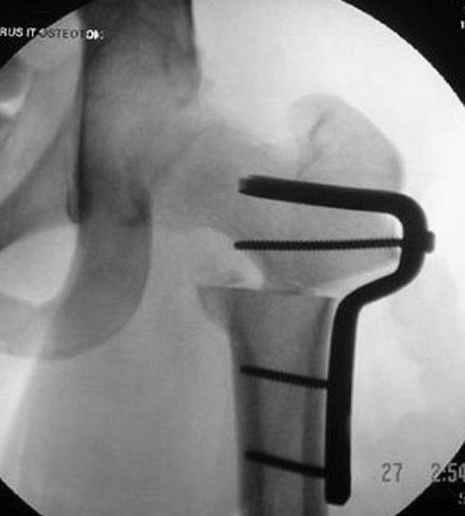

На рисунке N1 предоперационный план лечения ложного сустава шейки бедра- линия ложного сустава, угол и направление введения импланта, клиновидная остеотомия в градусах и миллиметрах, второй снимок после коррекции, расчет, на сколько удлиняется конечность и размеры импланта;

N3 рисунок окончательный снимок, после операции моя рентгенограмма должен выглядеть примерно как эта картина. На N4 снимке клин перед удалением; N5 послеоперации 3 нед.; N6 окончательная рентгенограмма.

варус при проксимальном отделе 95 градусной пластиной.